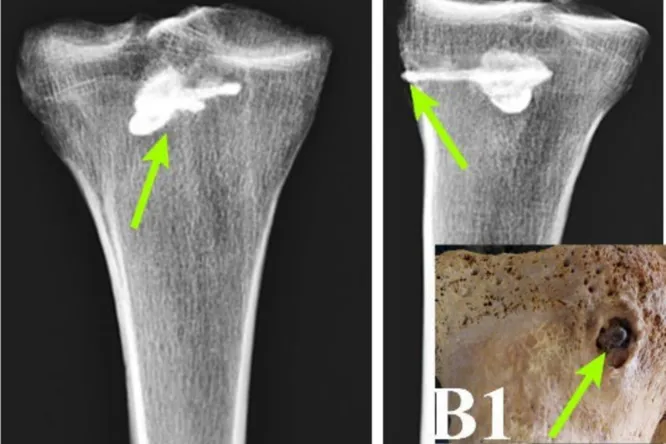

С помощью рентгенофлуоресцентного анализа — метода, определяющего химический состав вещества, — и компьютерной томографии ученые изучили сохранившиеся кости мужчины, а именно большеберцовую кость.

В ней они обнаружили металлический кусок стрелы. Это был не просто обломок, а целый наконечник с тремя лезвиями. Он был 44 мм в длину и 15 мм в ширину. Более того, его реконструкция полностью совпала по стилю с найденными ранее парфянскими стрелами.

Дальнейший анализ позволил ученым увидеть, что при жизни плотная костная ткань начала формироваться вокруг наконечника. Это означает, что после ранения человек остался жив, и его тело начало процесс заживления.

При этом исследователи не нашли признаков сильного воспаления или инфекции в кости. Это значит, что рана не гноилась и не вызвала заражение крови, которое в те времена почти наверняка привело бы к смерти.